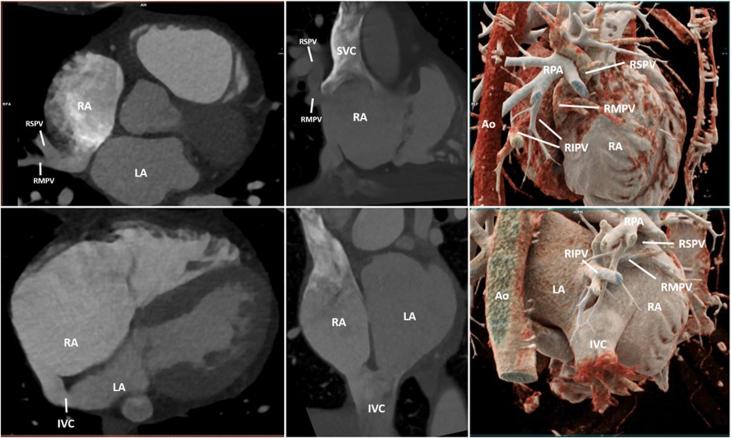

A female patient with multiple cryptogenic strokes was found to have a positive agitated saline study without evidence of atrial septal defect on transesophageal echocardiography. Cardiac computed tomography was used to diagnose partial anomalous pulmonary venous return (PAPVR) of the right superior and middle pulmonary veins associated with an inferior SVD. Three-dimensional printing was then used to aid in surgical planning.

Traditionally, an inferior SVD is associated with inferior PAPVR. This is a rare case of an inferior SVD with superior PAPVR that highlights the importance of multimodality imaging for accurate diagnosis and management.